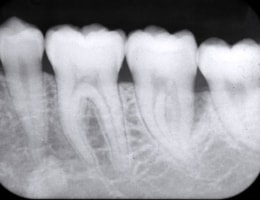

被曝量の少ない「デジタルレントゲン」を完備!

超高感度だから被曝量が軽減!子供さんにも優しいレントゲン!

デジタルレントゲンに使われているX線センサーは、デジタルならではの高感度!

照射時間が短縮され、より低線量でのレントゲン画像取得が可能となります。

また、各ユニットのデジタルモニターにも直接映像を映し出すことが出来るため、

当院のデジタルレントゲンは、

従来のフィルムを使用したレントゲン撮影に比べ、

人体に受ける放射線の量を、約1/4~1/10に抑える事が可能です。

大きなパノラマレントゲンは歯並びなど、全体像をつかむことにも有効的ですが、

現状を詳細に把握するため、小さいレントゲンを10枚撮って診断・治療をしております。

これにより歯石、歯周ポケット等も詳細に把握でき、緻密な治療を提供することが出来ます。